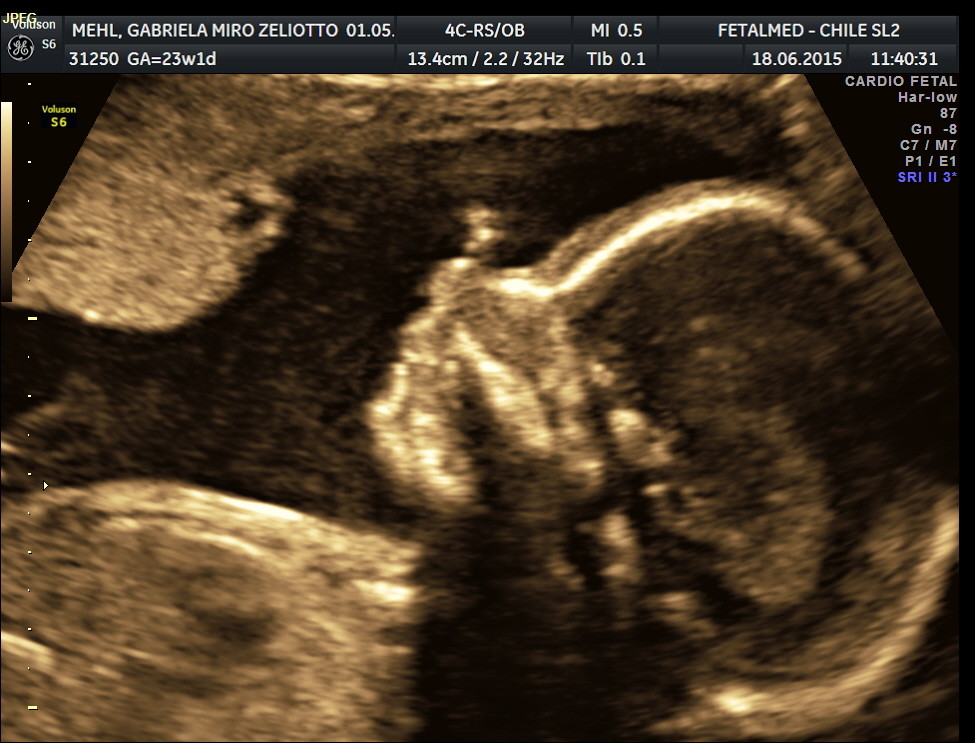

O bebê está perto de meio quilo, ainda muito magrinho, porém muito desenvolvido. Mede cerca de 26 cm da cabeça aos pés. Os cílios e as sobrancelhas estão agora formados e o cérebro começa a crescer rápido (um crescimento que dura até os 5 anos de idade após o nascimento). Se ele é um menino, seus testículos começam a descer da pelve para a bolsa escrotal. As pernas se aproximam do comprimento proporcional final em relação ao corpo.

Se você ainda não fez o ultrassom morfológico corra! A época ideal para você fazer este exame é entre 20 e 24 semanas de gestação.